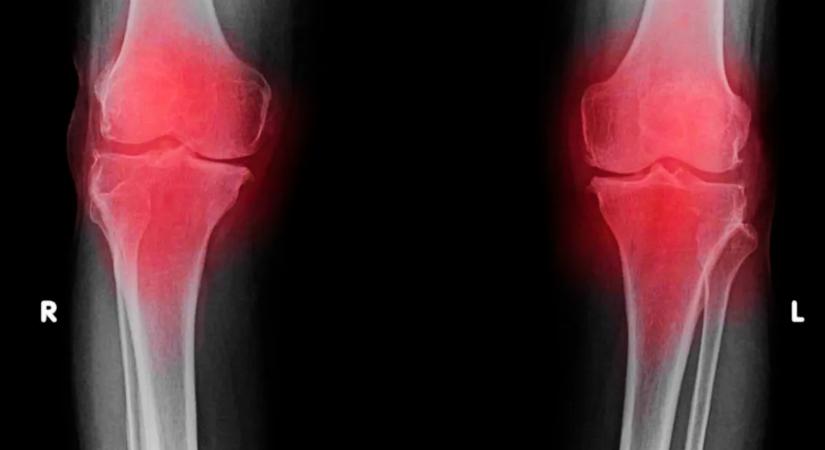

Vége a fájdalomnak: megoldást találhattak a magyarok tömegeit érintő betegségre

Újfajta gyógymód állhat rendelkezésre.